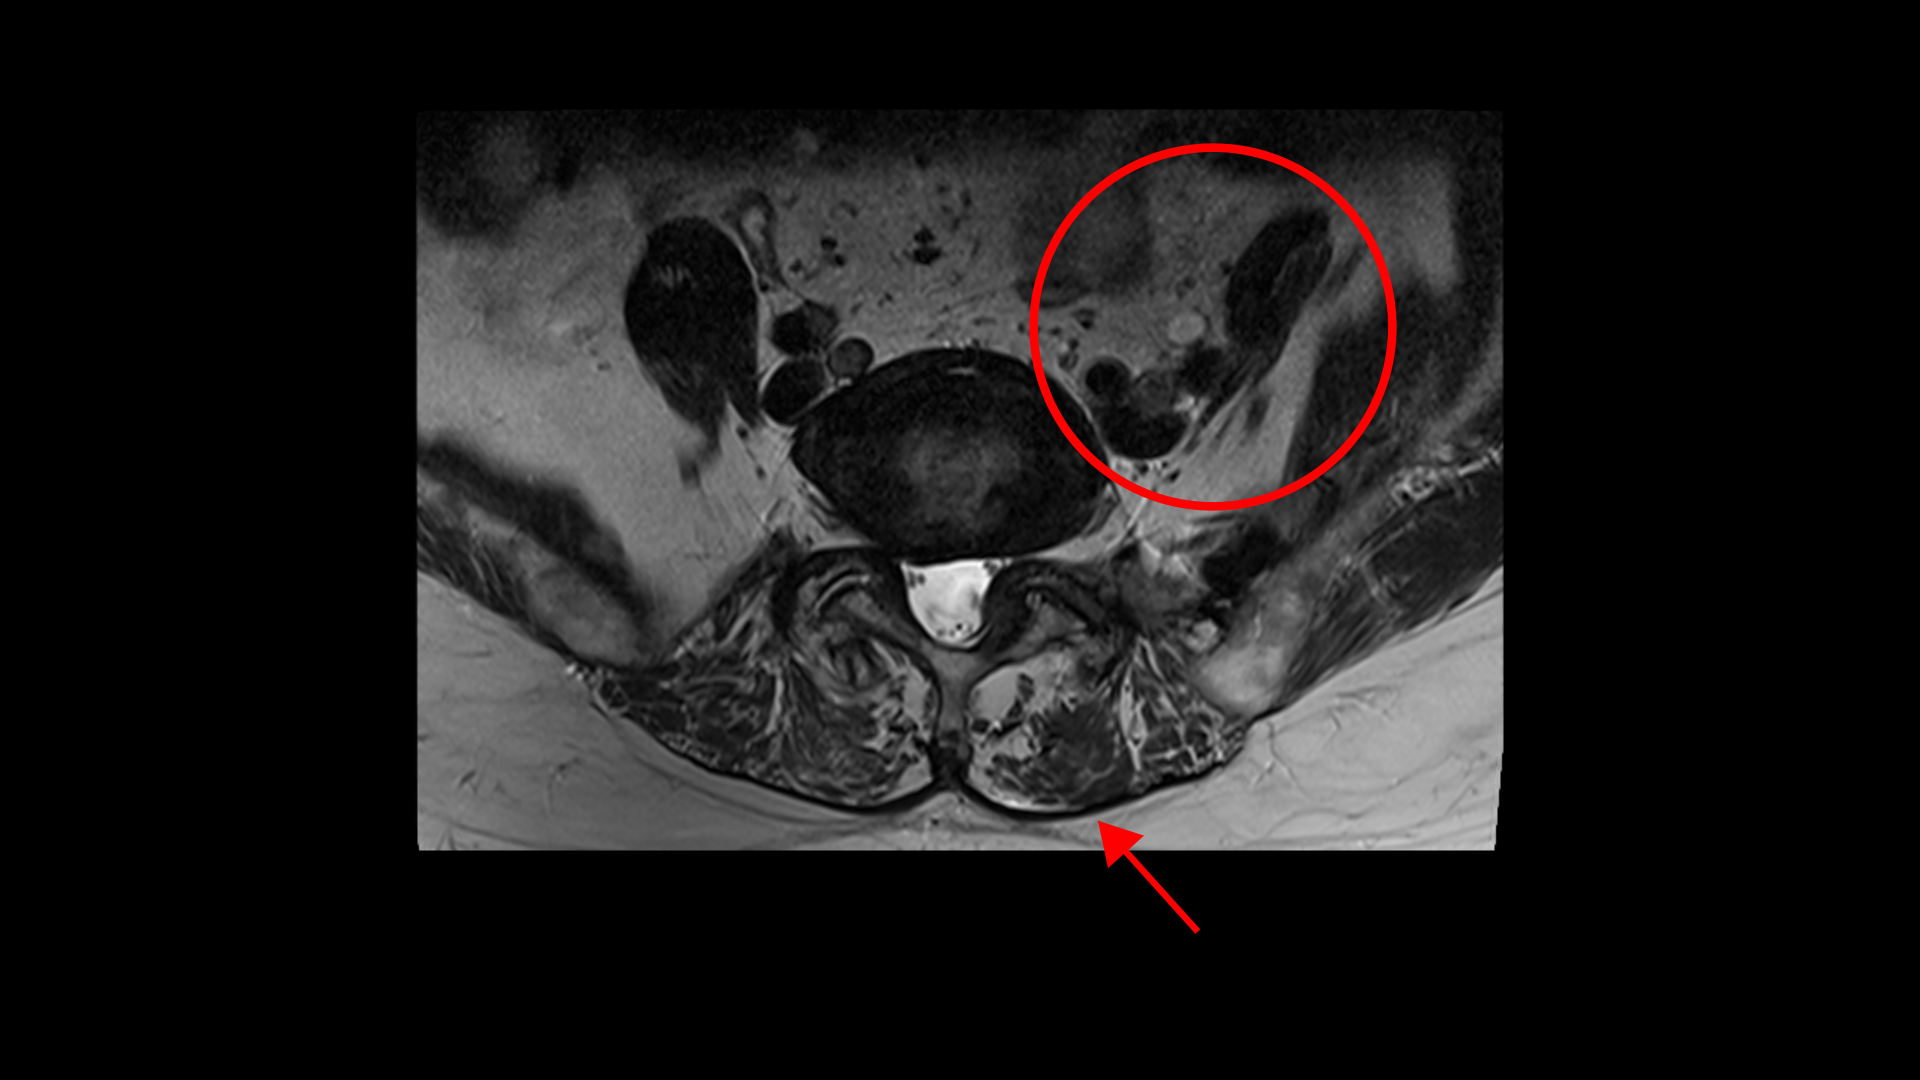

그런데 저희 모커리한방병원은 신경 만이 문제가 아니고 오히려 80세가 넘어갈수록 신경보다 근육 문제가 훨씬 더 중요하다고 말씀 드립니다. 신경구멍이 좁아지는 속도보다 70대 이후 80세가 넘어가면서 근육이 줄어들고 망가지는 속도가 훨씬 더 빠르다고 말이죠. 특히 신경이 자극 받고 눌리는 상태에서는 근육이 위축되고 빠지는 속도가 더 빨라집니다.

이 환자분의 근육을 MRI에서 보면 5번, 1번 마디에서 기립근과 장요근을 체크해봤을 때 기립근의 지방화 정도도 심하고 장요근, 특히 왼쪽 장요근은 거의 형체를 알아보기 어려울 정도로 위축이 심한 상태입니다.